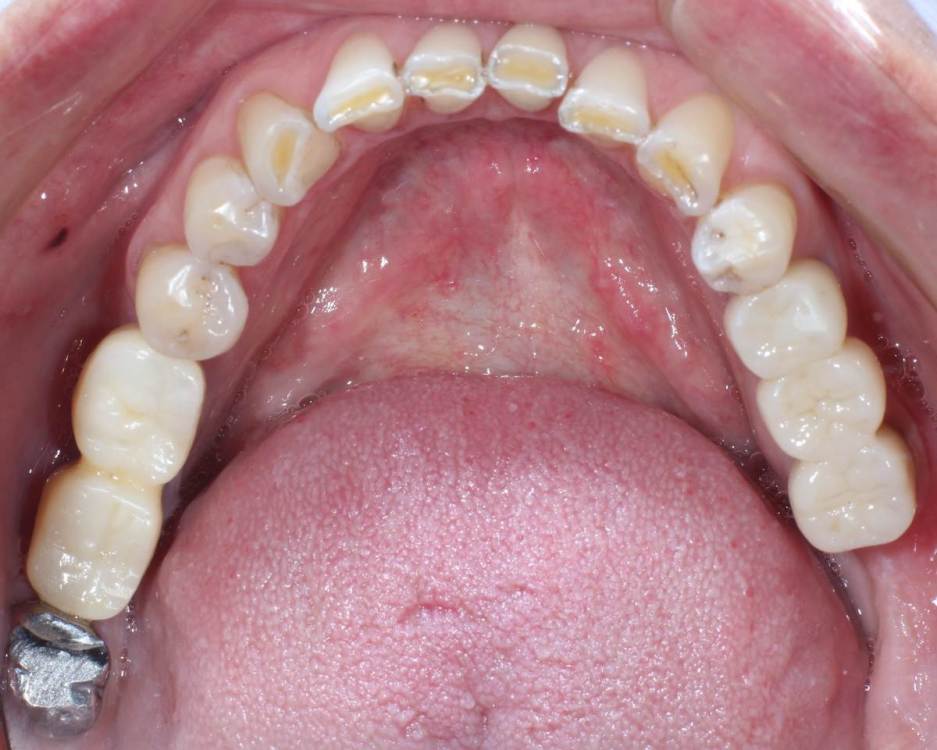

kuziy12 Опубликовано 2 ноября, 2020 Поделиться Опубликовано 2 ноября, 2020 Имплантация с синус лифтингом. Беда с позицией 2.3. Коронки на cad\cam, наносил розовую керамику и красил все сам. Сваливать не на кого) До: После имплантации: Формики: Десна: Постоянная конструкция: Улыбка: 3 Ссылка на комментарий

It'sGeorgy Опубликовано 3 ноября, 2020 Поделиться Опубликовано 3 ноября, 2020 даОбратите внимание, что там на 2.7 с гигиеной беда совсем. Думаю, что пища оттуда плавно может перекочевать под консоль. 2 Ссылка на комментарий

kuziy12 Опубликовано 9 октября, 2021 Автор Поделиться Опубликовано 9 октября, 2021 Дабы не плодить темы, выложу тут. Докрутил пациента полностью)) Ортопедия тоже моя. От переустановки импланта в области клыка отказалась. Ссылка на комментарий

Карен Аванесов Опубликовано 11 октября, 2021 Поделиться Опубликовано 11 октября, 2021 Ну вот, поздравляю Вас, получили благословение от Большого Зеленого, таперча работе служить 10 лет не меньше. 16 часов назад, Большой Зеленый сказал: Проблемы будут обязательно... а меня стертый клык насторожил, а работа жить будет, во рту чисто. 1 Ссылка на комментарий